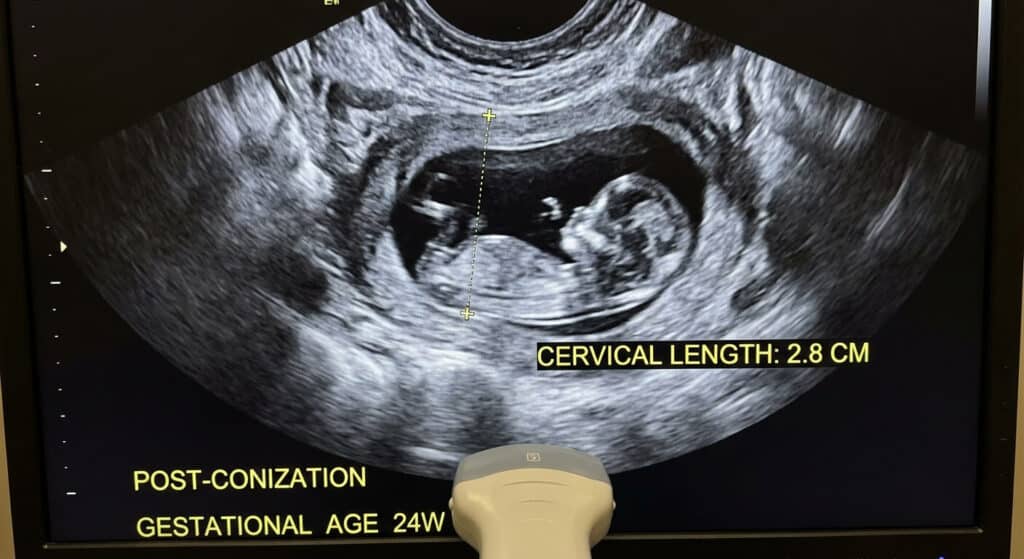

Le problème principal d’une conisation itérative (répétée) est la réduction de la hauteur du canal cervical. Un col « standard » mesure environ 30 à 40 mm. Après deux conisations, il peut ne rester que 10 ou 15 mm de tissu sain. Cette réduction fragilise la fonction de « verrou » que joue le col pendant la grossesse, indispensable pour maintenir le fœtus à l’intérieur de l’utérus jusqu’au terme.

« Avant de proposer une deuxième conisation, je vérifie toujours la réserve de tissu par échographie cervicale. Si le col est déjà court, je préfère parfois proposer un traitement au laser pour vaporiser les lésions en surface plutôt que de recouper un morceau. Le laser est moins invasif pour la structure du col. Si toutefois la réopération est inévitable, nous informons la patiente qu’un cerclage définitif ou une surveillance échographique hebdomadaire sera nécessaire lors de sa future grossesse. »

📏 Comment savoir si mon col est assez long pour une deuxième opération ?

Seule une échographie endovaginale réalisée par un spécialiste peut mesurer avec précision la « longueur fonctionnelle » de votre col. Si cette longueur est supérieure à 25 mm, une seconde conisation est généralement envisageable sans trop de risques. Si elle est inférieure, le chirurgien devra utiliser des techniques de micro-conisation ou de vaporisation laser pour économiser chaque millimètre de tissu.